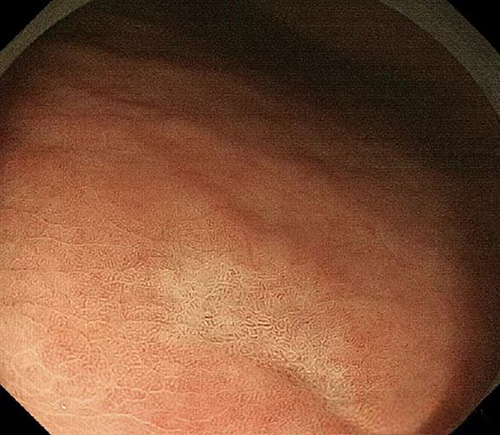

白光内镜特征:位于胃体上部或胃底、上皮下和黏膜下肿瘤样隆起性病变、白色调或褪色调、扩张的树枝状血管、背景黏膜上无萎缩性变化;放大内镜特征:无明显DL、腺开口部(CO)的扩张、窝间部(IP)的扩张、不规则的微血管。

白光